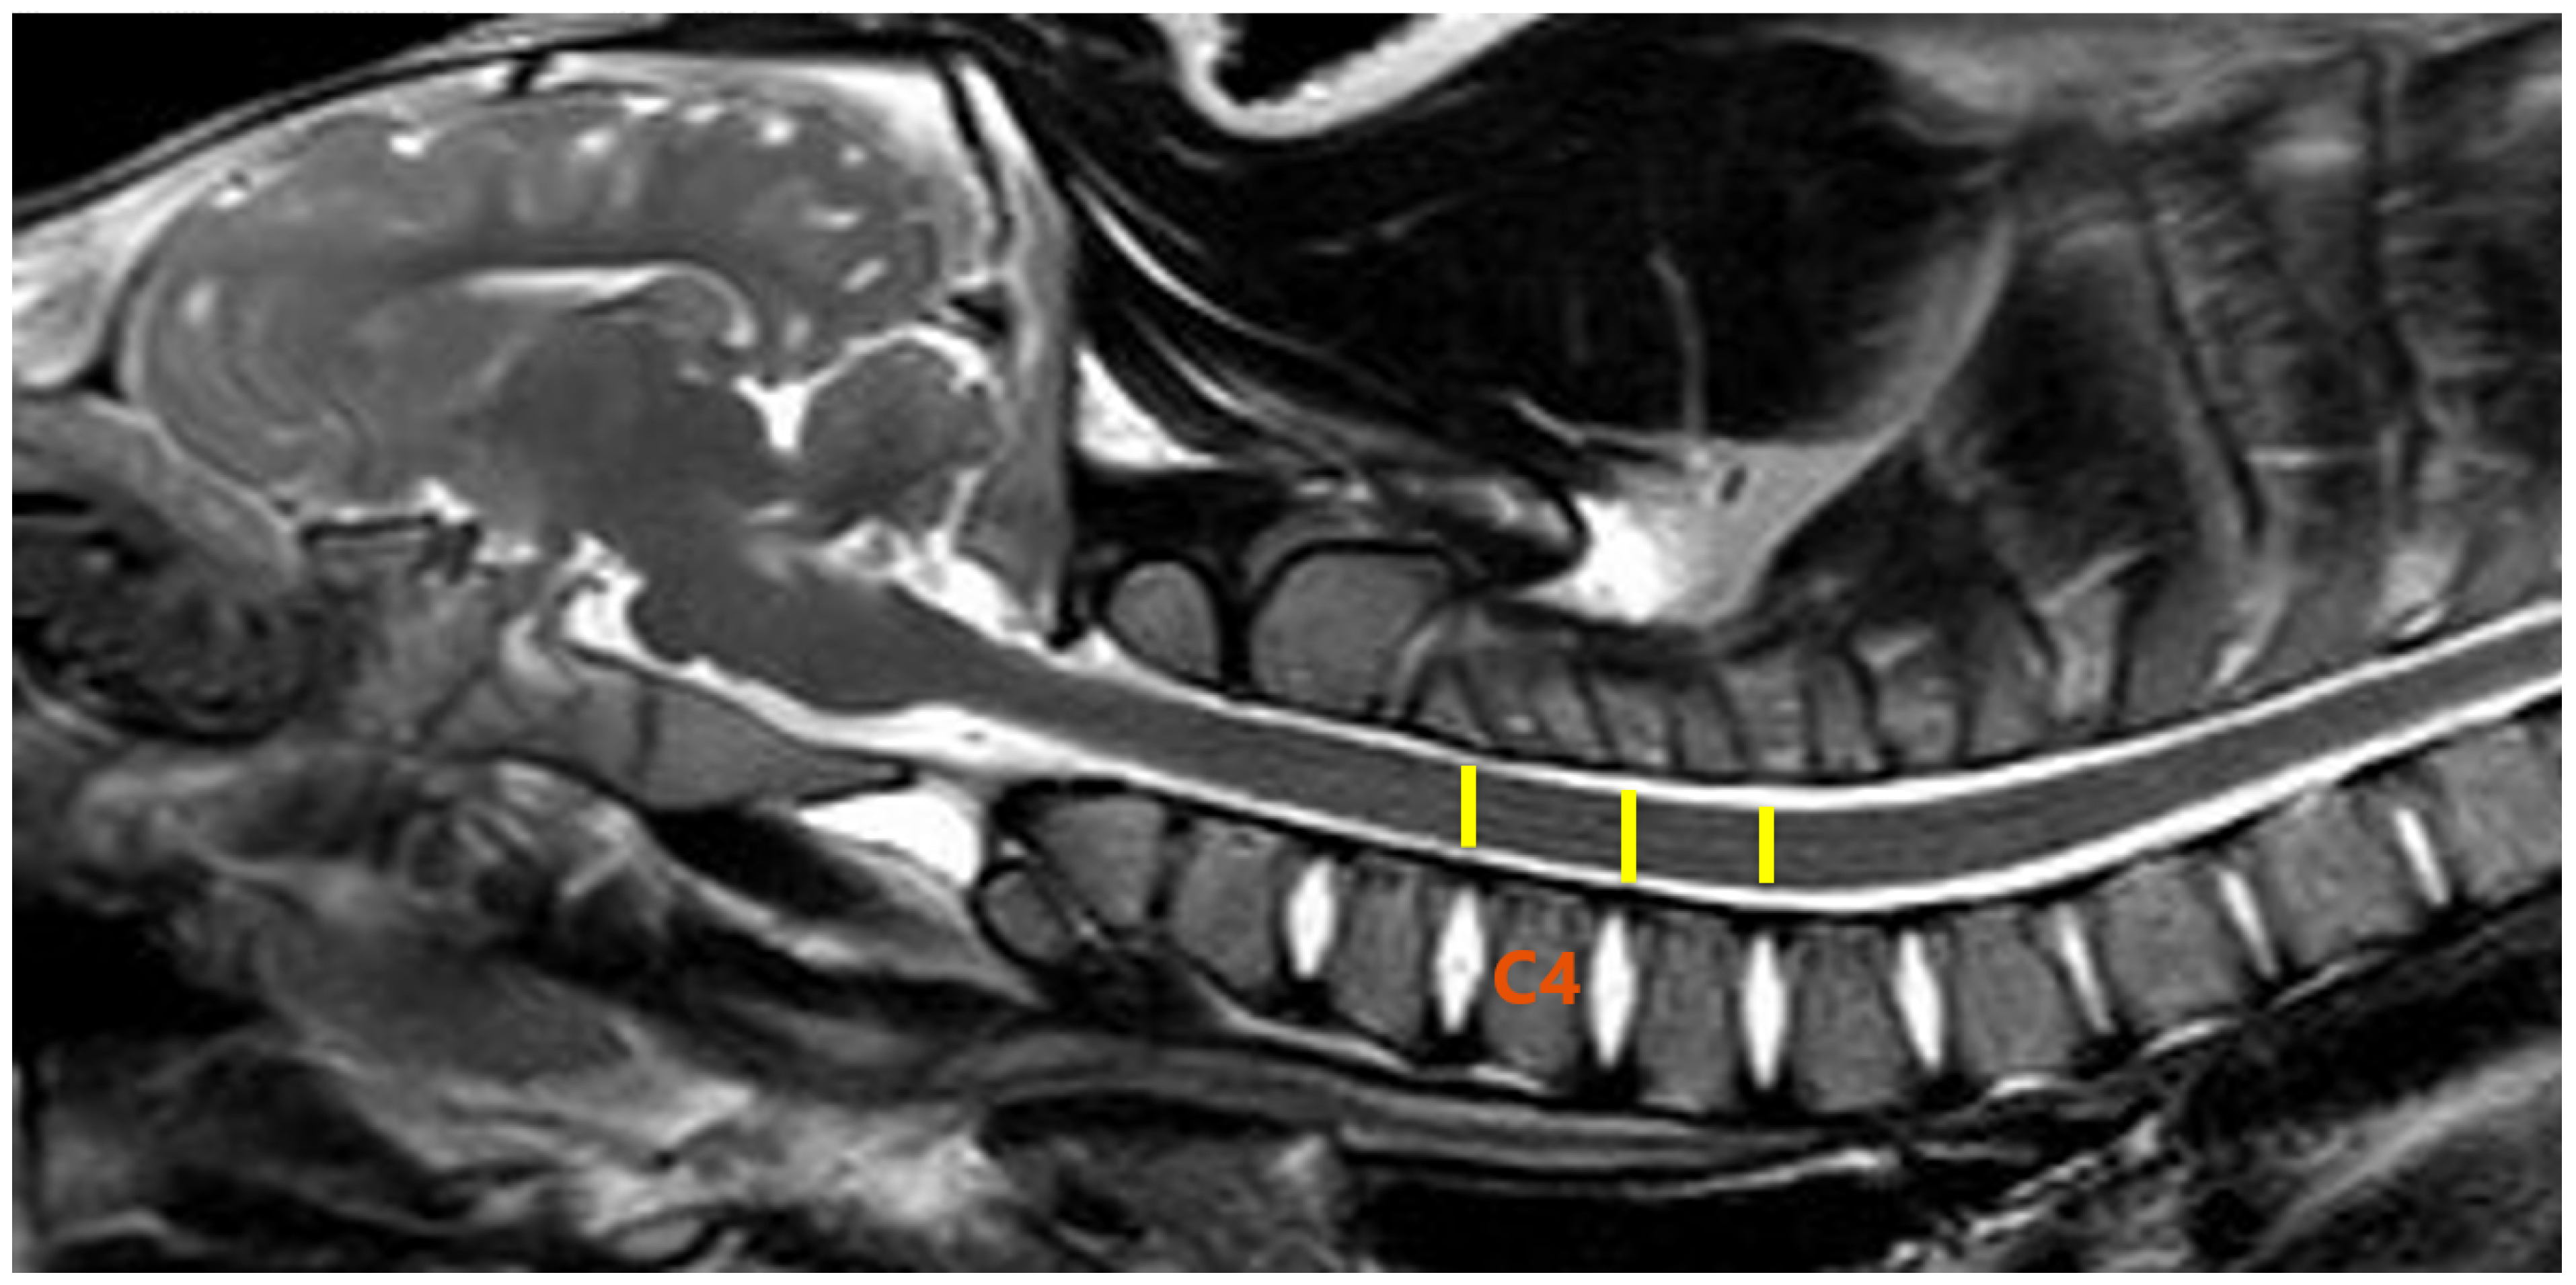

2.3. MR Imaging and DTI Protocol

2.4. Image and DTI Analysis